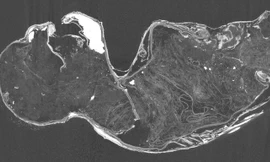

Một phân tích mới về xác ướp "nàng tiên cá bị ma ám" được tìm thấy trong một ngôi đền Nhật Bản đã tiết lộ chính xác nó là gì: Một tạo vật rùng rợn hơn cả những gì được dự đoán trước đây.